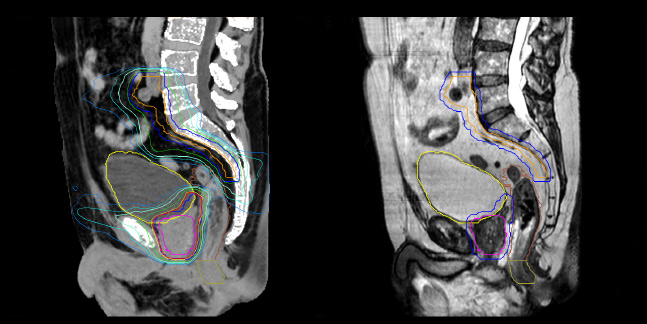

MR-based contouring and planning

MRCAT is primary image dataset for dose calculation (left).

3D T2W TSE MRI with 36 cm Field-of-View is used for delineation of prostate and organs at risk (right).